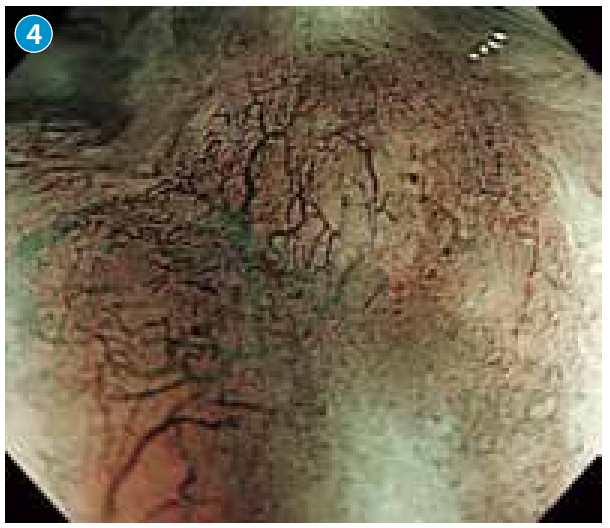

●观察到缺乏环状、不规则、树枝状的血管网。判断为不规则的R型血管(→)

。

●综合判断病变为以上皮下发育为主体的黏膜下肿瘤。微细血管为不规则网状的R型血管。疑为特殊组织类型食管癌。

NBI下放大观察到的R型微细血管从表层到深处,在组织学上显示逐渐变粗的倾向。